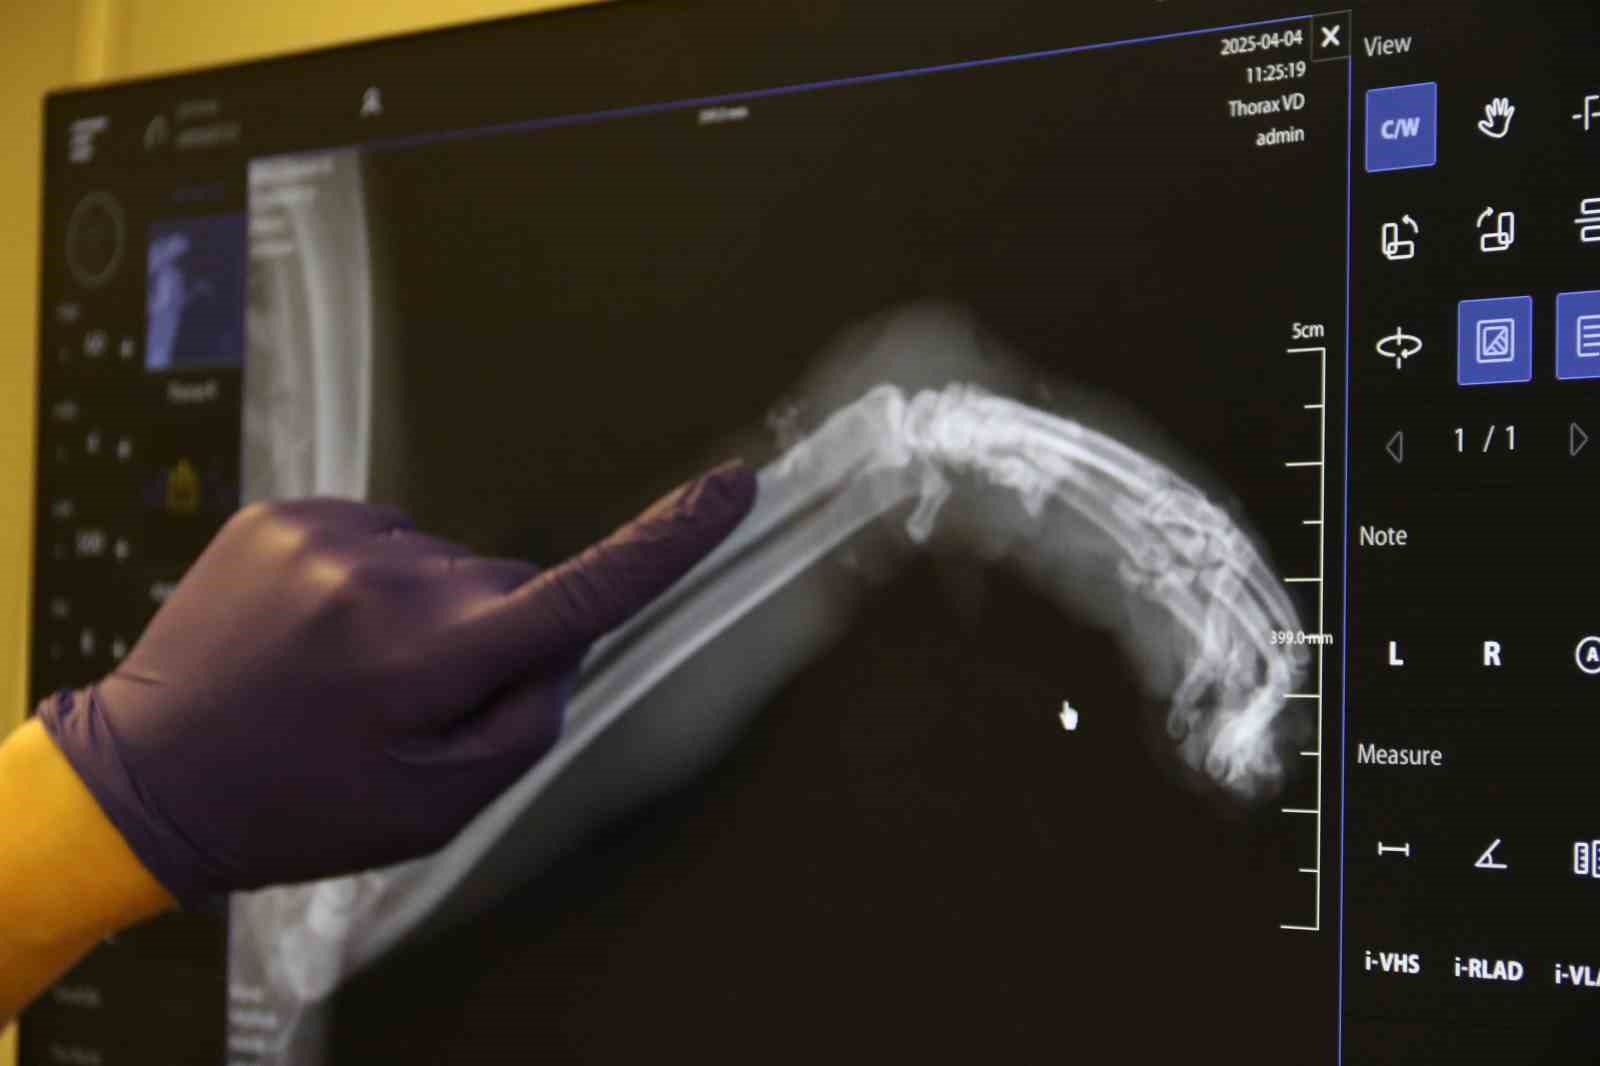

Geçtiğimiz günlerde Odunpazarı Emek Mahallesi’nde kimliği belirsiz kişi veya kişilerce bir kedinin sol ön bacağına paket lastiği takıldı. Kedinin patisine birkaç kez sıkı bir şekilde dolanan paket lastiğin talihsiz hayvanın ayağının şişmesine neden oldu. Bunu fark eden bir hayvansever kediyi Kurtuluş Mahallesi’ne bulunan bir veteriner kliniğine götürdü. Burada tedavi altına alınan hayvanın öncelikle patisindeki lastik çıkarıldı. Sol ön ayağında ödem biriken kedinin patisinin röntgeni çekildi. Antibiyotik tedavisi uygulanan kedinin ayağının kangren olma riski ve buna bağlı olarak ayağının ampute edilme ihtimali var. Tedavi altına alınan kedi gözlem altında tutuluyor.

Kedinin tedavi süreci hakkında bilgi veren Veteriner Hekim İlayda Ulus, "Kedi saat 4 gibi geldi kedimiz. Bacağı aşırı derecede şişmiş, ödenmiş şekilde geldi. Biz ilk başta kırık sandık. Ama muayene ettiğimizde 4-5 kere bağlanacak şekilde lastiğin burasını boğmuş olduğunu gördük. Bu bilinçli şekilde yapılmış. Dolaşım bozmak adına. Kimin yaptığını bilmiyoruz. Hasta sahibimiz getirdi çok üzülerek. Biz de tedaviye başladık şu anlık. Sokak kedisi, birisi sadece dükkanında bakıyormuş, gidip geliyormuş. Bir haftadır yokmuş kedisi. Aramışlar, birisi haber vermiş tasmasından bularak o şekilde geldi. Oradaki tüyleri özellikle tıraş ettik. Ölü dokuları aldık. Baya bir kan toplamış ve ölü dokular birikmiş. Onları temizledik, tıraş ettik. Antibiyotik tedavisine başladık. Şu anda sabah akşam olacak şekilde krem sürüyoruz. Yarın tedavisi yapıyoruz. Oradaki kan akımını hızlandıracak kremler, özellikle fizik tedaviler uyguluyoruz. Şu anda 3-4 gün takip edeceğiz. Eğer iyileşme görmezsek amputeye doğru gidebiliriz. Şu anda sol ön ayağını kaybetme ihtimali var. Birkaç kere böyle tasma boğulmuş şekilde geldi, boyundan yara almış kediler. Başka tekme çok geldi, göğüs kırıkları. Bu tür vakaları gördük. Onların ağzı var, dili yok. Bizden daha daha masumlar. Bu şekilde olması bizi çok üzüyor, derinden üzüyor. Hayvan sevmeyen, insan sevemez. Bu şekilde çok daha duyarlı ve dikkatli olmalarını bekliyoruz" dedi.